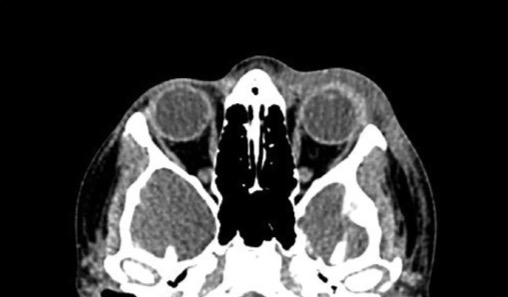

Аксиальная компьютерная томография головного мозга и орбит. Отмечается отек мягких тканей в предсептальной области. Абсцесса или внутричерепного расширения не обнаружено.